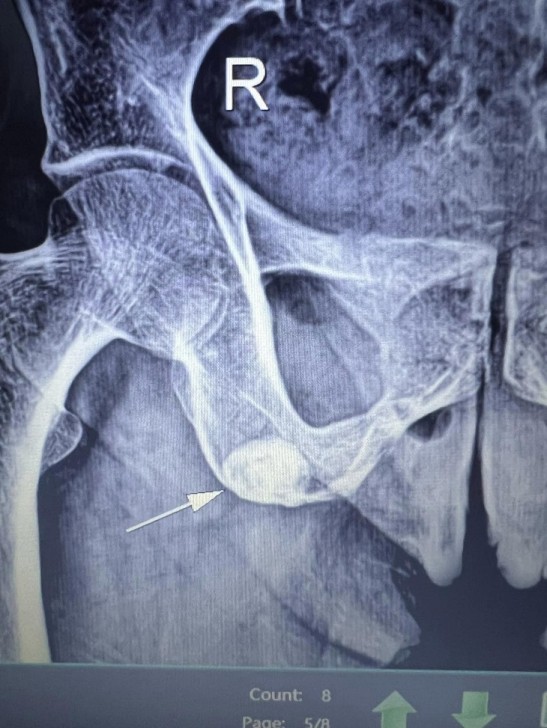

AFN.az xəbər verir ki, tanınmış həkim Aydın Əliyev bu sahədə vəziyyətin getdikcə ağırlaşdığını bildirib. O, xəstələrdən birinin müayinə nəticələrini paylaşaraq bunları yazıb: “Onkoloji xəstəliklərin müayinə və müalicəsinin hələ də icbari tibbi sığorta tərəfindən qarşılanmamasının daha bir qurbanı. Sağ qamış sümüyündəki törəmənin maddi imkansızlıq səbəbindən vaxtında və sistemli müalicə və ya əməliyyat edilməməsi səbəbindən fəqərələrə, qabırğalara, kürək, çanaq sümüklərinə, ağciyərə çoxsaylı metastazları. Demək olar ki, adam həyatını itirib”.